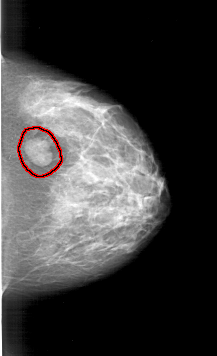

FILE: A_1394_1.RIGHT_MLO.OVERLAY

TOTAL_ABNORMALITIES 1

ABNORMALITY 1

LESION_TYPE MASS SHAPE LOBULATED MARGINS CIRCUMSCRIBED

ASSESSMENT 4

SUBTLETY 5

PATHOLOGY BENIGN

TOTAL_OUTLINES 1

BOUNDARY